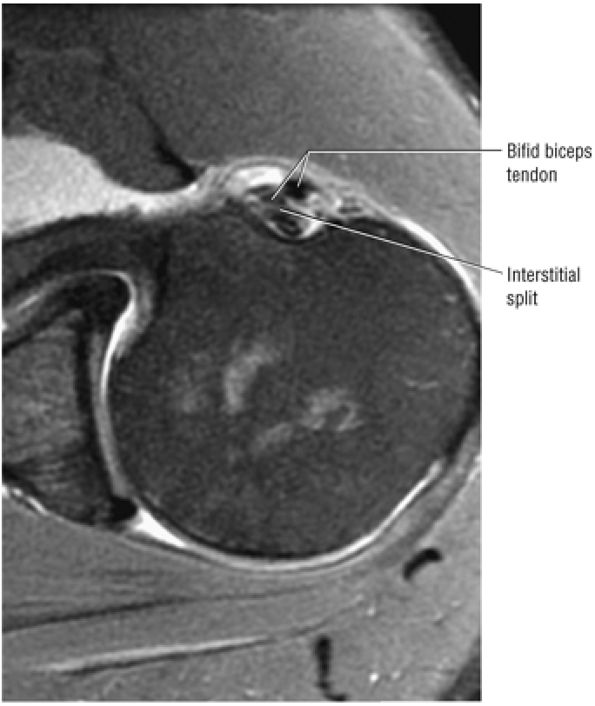

FIGURE 8.71 ● (A) Double biceps with two tendons inserting into the supraglenoid tubercle. (From

) A bifid biceps tendon is shown in its extra-articular course on an axial T1-weighted arthrogram (B) and a corresponding gross dissection (C). |